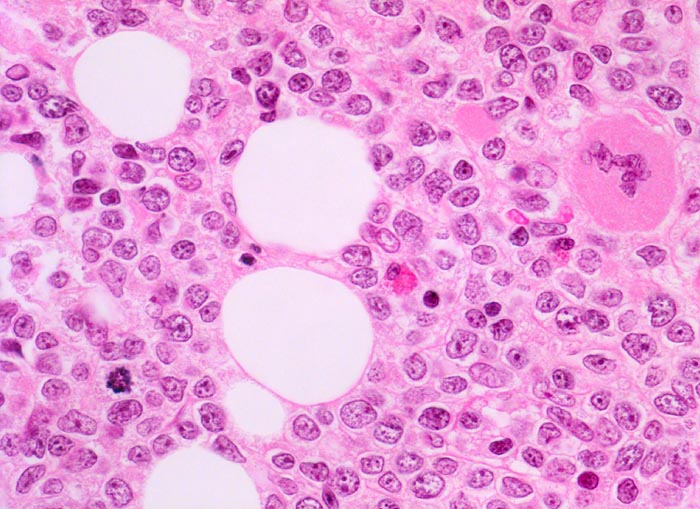

• Mittelgrosse Lymphoblasten mit wenig Zytoplasma.

• Kerne mässig polymorph, oval, teils mit Kerneinkerbungen. Feine Nukleolen. Lockeres Chromatin.

• Zahlreiche Mitosen.